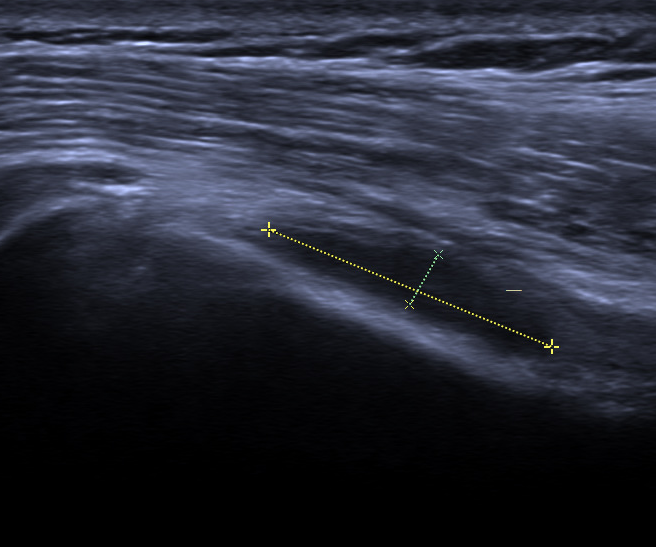

2.冈上肌腱炎或者冈上肌腱钙化